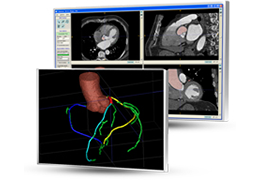

Traditional multi-planar slicing

Multi-planar slicing.

Oblique slicing.

Side-by-side comparative assessment for pre- and post-operative scans.